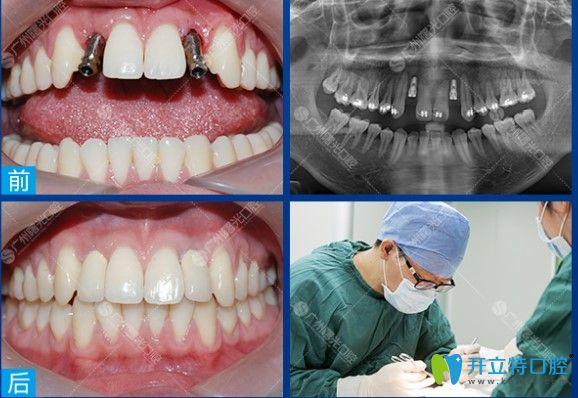

- 案例沟通:要求查看医生过往类似案例,了解术后效果与患者反馈,尤其是全口、半口等复杂种植案例。